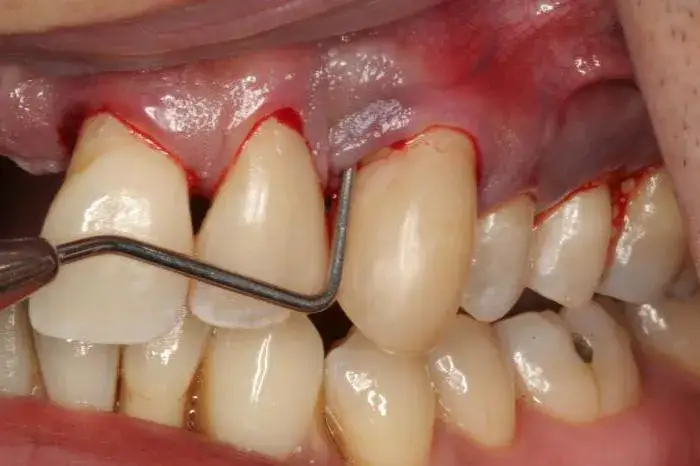

Zmiany w jamie ustnej – dowiedz się, do jakiego lekarza się udać i kiedy to pilne. Poznaj przyczyny, objawy i metody leczenia. Sprawdź, jak wygląda diagnostyka.

Włókniak jamy ustnej objawy – jak rozpoznać, czy jest groźny i kiedy udać się do lekarza? Sprawdź, jak wygląda leczenie, usuwanie i diagnostyka tej zmiany.